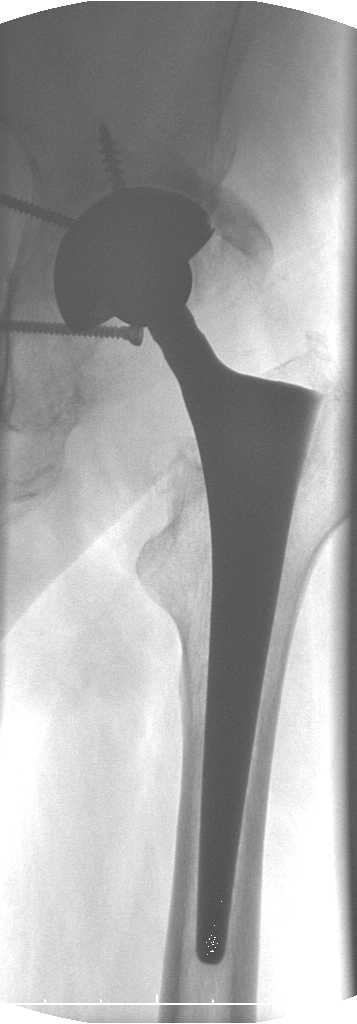

Уважаемые коллеги.В 3 Центральный Военный Клинический Госпиталь имени А. А. Вишневского, что в Красногорске, Московской области, в отделение эндопротезирования крупных суставов поступил пациент 1960 года рождения Жалобы при поступлении: на боли в области левого тазобедренного сустава (больной указывает на точку расположенная в середине условной линии между седалищным бугром и большим вертелом), усиливающиеся в начале ходьбы, при опоре на левую ногу с иррадиацией болей по наружной и наружно-задней поверхности левого бедра, левый коленный сустав; снижение объема движения в левом тазобедренном суставе, снижение опорной способности левой нижней конечности, хромоту на левую ногу, необходимость использования дополнительной опоры (костыли) при ходьбе, снижение объема двигательной активности из за болей в суставе.В анамнезе: Со слов больного, согласно медицинских документов, в 1989 году получил травму левой нижней конечности: закрытый перелом левой вертлужной впадины с центральным вывихом головки левой бедренной кости. Лечился консервативное. В процессе лечения сформировался посттравматический артроз, укорочение левой нижней конечности до 5 см. 25.04.2005 года в Подольском Окружном Госпитале Министерства Обороны выполнено: одномоменто, остеосинтез заднего края вертлужной впадины фрагментом резецированной головки бедренной кости и тотальное эндопротезирование левого тазобедренного сустава бесцементным эндопротезом "VERSIS ET" с бесцементной чашкой TRILOGY. Послеоперационный период осложнился ранним нагноением области эндопротеза, в результате санаций очага инфекции и антибиотикотерапии, активного промывного дренирования антисептиками, послеоперационная рана зажила. После операции, со слов больного, через два месяца в полном объеме стал нагружать левую нижнюю конечность. В течение полгода, после операции чувствовал себя вполне удовлетворительно. С марта 2006года стал отмечать появление болей в области тазобедренного сустава, то в области паха, то в области левой ягодицы. С августа месяца отмечает те жалобы, с которыми он сейчас к нам обратился. Температура тела, после заживления раны, нормальная. В анализах крови, лейкоциты около 7 тыс, формула нормальная, СОЭ 12 мм ч. Локально: при осмотре обеих нижних конечностей, анатомическая ось конечности не нарушена; отмечено относительное укорочение левой н\конечности на 1.5 см., гипотрофия мышц левого бедра 3 см, голени 2 см, симптом. Объем движений в тазобедренных суставах: правый~ сгибание- 60 гр, разгибание-180 гр ,отведение- 35 гр, левый~ сгибание- 110 гр , разгибание-170 гр , отведение-15 гр. Контуры других суставов н/конечностей обычные, объем движений в них не страдает. Пульсация на артериях конечностей удовлетворительная. Неврологические нарушения конечностей отсутствуют, рефлексы на обеих н/конечностях одинаковые, чувствительных нарушений нет. Осевая нагрузка на левую нижнюю конечность вызывает боль в точке расположенная в середине условной линии между седалищным бугром и большим вертелом. Отмечается пигментация и пастозность нижней трети обеих голеней и стоп, характерная для посттромботической болезни. На Цветном дуплексном сканировании сосудов нижних конечностей: Нестенозирующий атеросклероз обеих бедренных и подколенных артерий . Гемодинамически значимых препятствий кровотоку в магистральных артериях ног не выявлено. Глубокие и поверхностные вены нижних конечностей проходимы. Умеренная недостаточность клапанов подколенных вен. Данных за тромбоз глубоких вен на момент осмотра не получено.А вот что пишет наш рентгенолог: На серии рентгенограмм области левого тазобедренного сустава определяется тотальный бесцементный эндопротез. Вокруг тени чашки эндопротеза определяется ободок остеорезорбции. Кроме того, визуализируется деформированный костный винт фиксирующий консолидированный отломок вертлужной впадины, вплотную прилегающий к тени чашки эндопротеза. Заключение: Рентгеновские признаки нестабильности чашки тотального эндопротеза. Лучевая нагрузка: 6 мЗв. У нас в отделении разошлись мнения: начальник мой утверждает, после сравнения снимков, принесенных больным от августа и октября 2006года и наших рентгенснимков, что у больного нет нестабильности вертлужного компонента, и что надо назначит курс консервативной терапии: препараты кальция, миакальцик, увеличить осевую нагрузку на левую нижнюю конечность, ЛФК направления на укрепление мышц бедра, ягодиц, физиолечение. А я утверждаю, что у больного клиника нестабильности вертлужного компонента, и необходима ревизия вертлужного компонента, не исключено даже наличие инфекции под чашкой эндопротеза (не смотря на отсутствие клинических признаков инфекции). В результате проводимой консервативной терапии, боли у больного усилились. Помогите рассудить нас, мы готовы выслушать ваши мнения по этому поводу. С уважением Батал Шушания.3 ЦВКГ имени А. А. Вишневского

Ув. Коллега.Четких рентгенологических признаков нестабильности вертлужного компонента действительно нет. Здесь, кроме нестабильности, можно искать причину в поясничный отдел позвоночника(Hip-spain синдром - всё-таки 15 лет ходил с укорочением),либо сделать спиральный КТ и посмотреть, нет ли несращения в области старого перлома вертлужной впадины. Зачастую ложные суставы подвздошной, седалищной, а иногда и лонной костей являются причинами несостоятельности эндопротезов.

Уважаемый д-р Батал,

Ситуация не столь однозначная как Вам это видится. По подробно описываемой клинике с большей вероятностью речь идет о проблемах

поясничного отдела позвоночника. Есть зона остеолиза вокруг чашки, но как правило, дополнительный винт держит чашку достаточно хорошо, и даже при наличии микроподвижности, это не сопровождается столь ярким болевым синдромом. Поэтому, я бы сделал следующее: МРТ позвоночника, пункцию ТБС для исключения инфекционного процесса. Ревизию рассматривал бы как крайний вариант, учитывая выполненную костную пластику и отсутствие явных признаков нестабильности.

уважаемый коллега, Антон Вакуленко. Спасибо за четкий, расписанный по пунктам план действий. При поступлении пациента в отделение, я думал точно как вы. Но на следующий день, выполнил многопроеционное рентгенисследование, показал невропатологу, и доложил начальнику отделения о больном.После разбора пришли к следующему, да у больного действительно нестабильность вертлужного компонента, есть зона лизиса в месте костного аутотрансплантата, а в месте фиксаци чашки деротационным винтом четко выраженный контакт чашки с костной тканю. Мы пришли к выводу,что лизис костного аутотрансплантата из за осевой перегрузки на фоне незавершенного ремоделирования (вес больного 130 кг). Потому мы и приняли план вышеуказанного лечения. Провели беседу с больным, больной согласился с нами. Через 3-6 месяцев мы оценим эффективность лечения и доложу. Возможно и придется тогда идти на ревизию с заменой только вертлужного компонента а может и придется удалить весь эндопротез с установкой спейсера.. посмотрим.....

> компонента, есть зона лизиса в месте костного аутотрансплантата,

> а в месте фиксаци чашки деротационным винтом четко выраженный

> контакт чашки с костной тканю. Мы пришли к выводу,что лизис